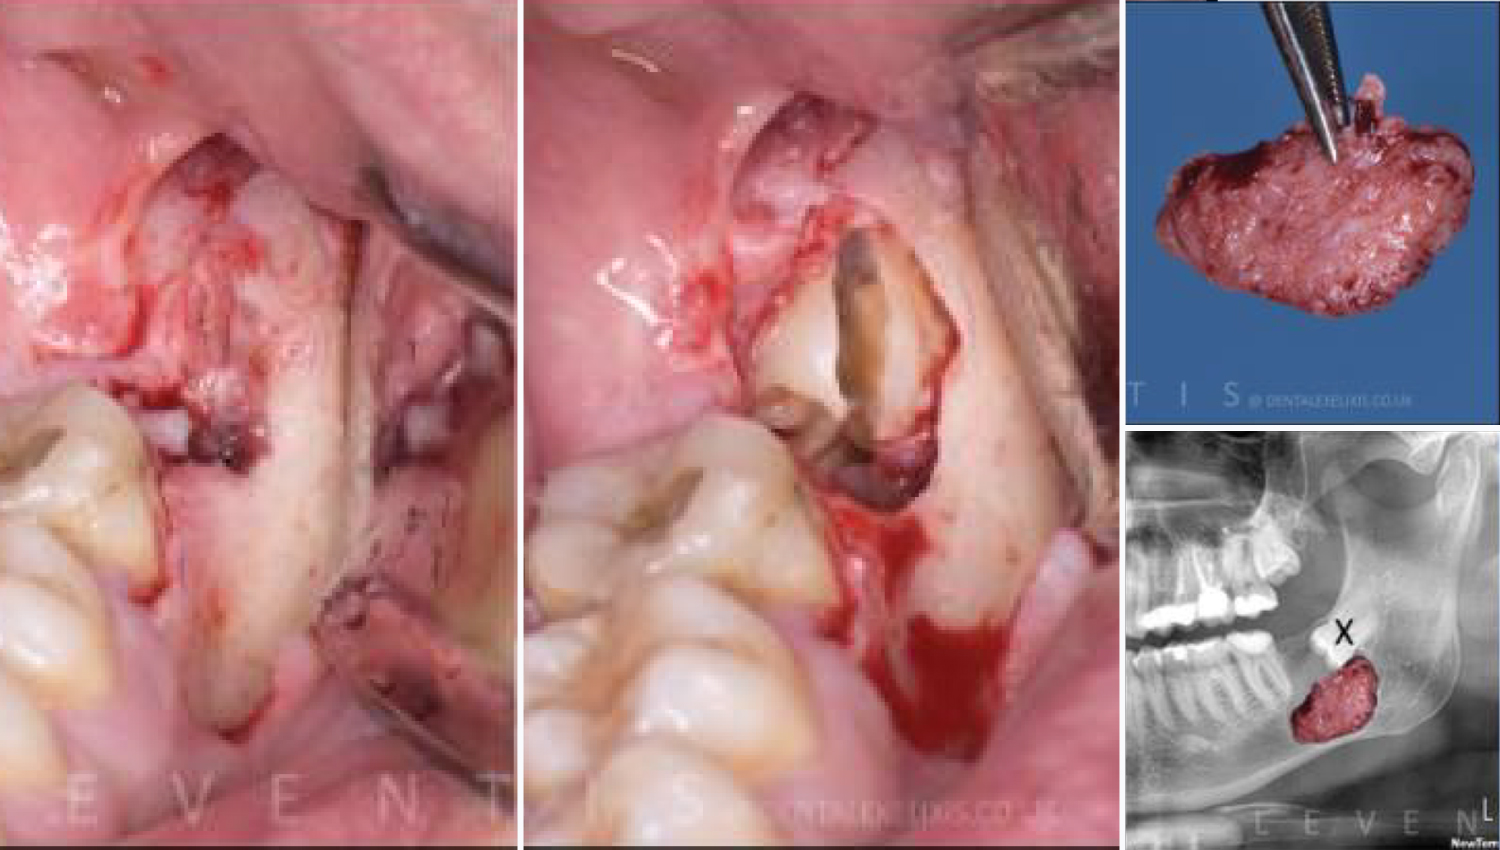

3. Surgical removal of an impacted third molar and removal of the associated dentigerous cyst.